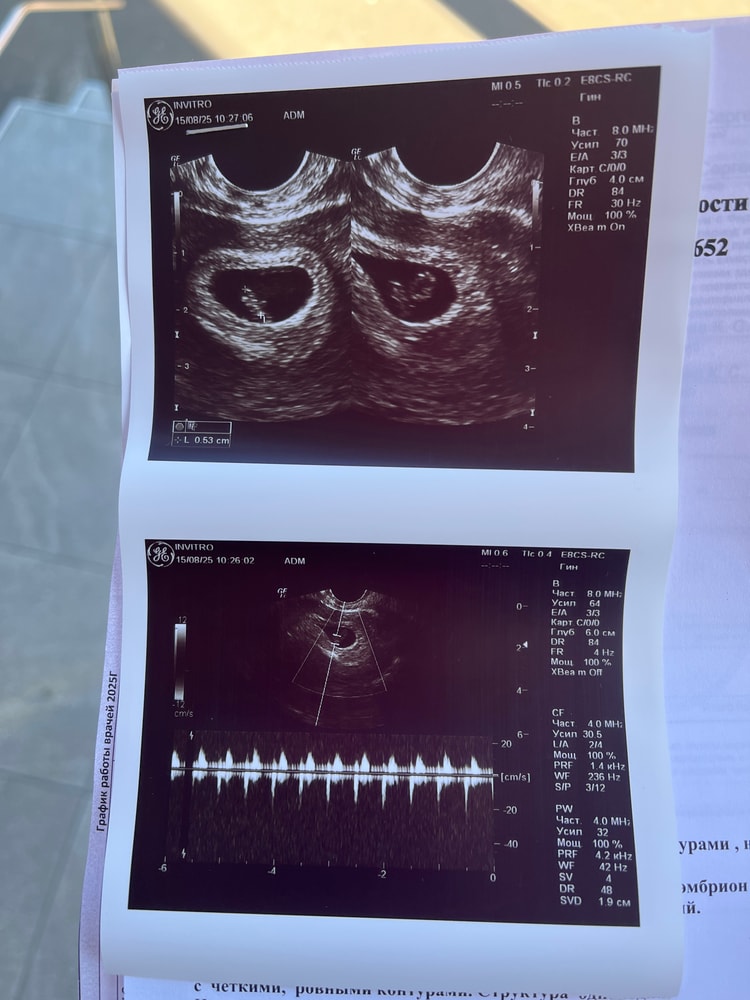

Спустя 10 дней после предыдущего узи, где мы нашли ПЯ, я вновь отправилась на узи и мы нашли эмбрион 😍послушали сердце +-170уд.мин, ктр 5,3мм, пя- 17мм